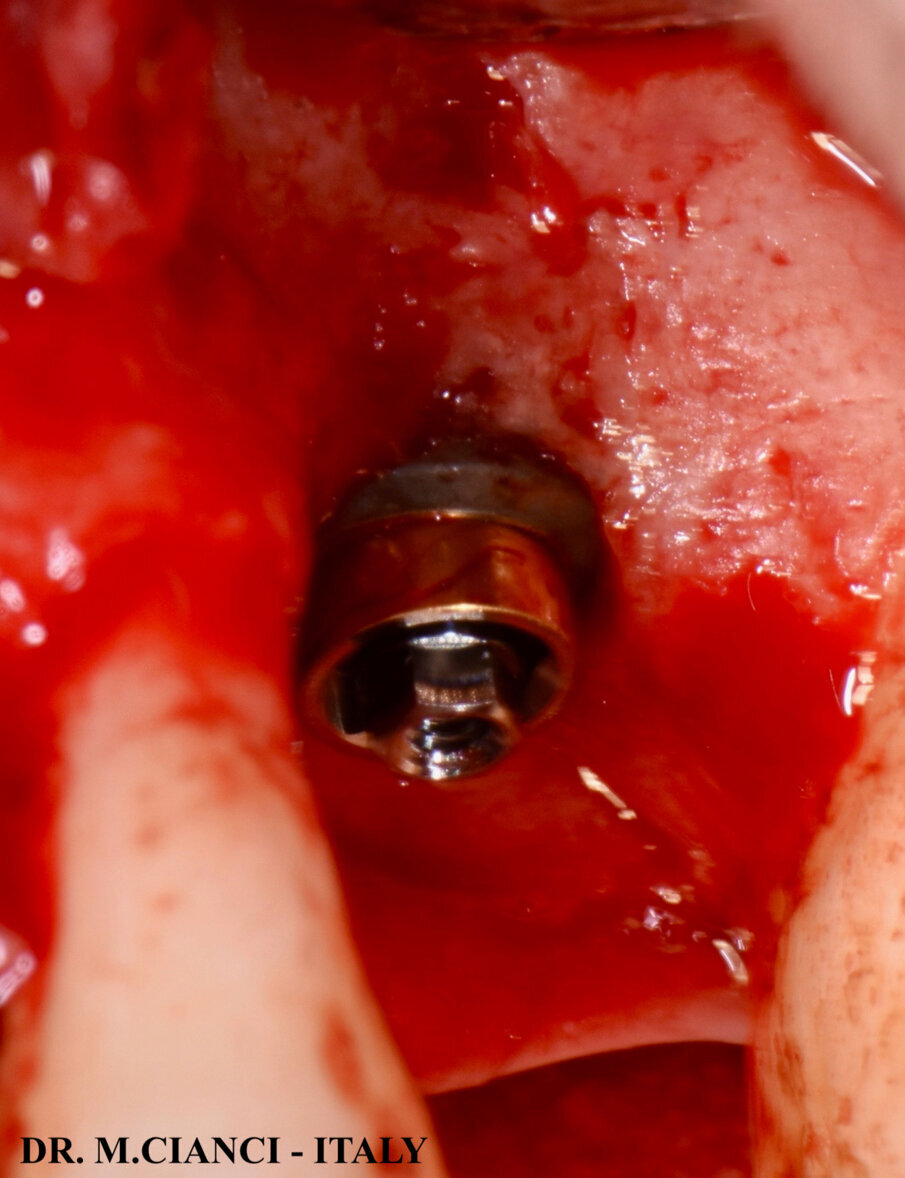

Sollevato un lembo a spessore totale vestibolo-palatale sono state utilizzate frese di diametro progressivo sottopreparando il tragitto implantare al fine di ottenere una stabilità primaria necessaria ad eseguire il carico immediato: ultima fresa di diametro 4,8 mm utilizzata solo fino a 4 mm di profondità sottopreparando l’apice del tunnel osseo prima di inserire l’impianto. Gli ultimi 0,5 mm sono stati fresati con una speciale fresa a taglio frontale di diametro 4,5 mm che ci ha permesso di sollevare la membrana di Schneider mantenendola integra (Fig. 6). A questo punto, una volta verificata la negatività della manovra di Valsalva, è stata inserita sul fondo della preparazione una membrana di fibrina autologa elaborata con la frazione 1 del PRGF Endoret® , meno ricca di fattori di crescita piastrinici, a protezione della membrana sinusale e con un condensatore abbiamo eseguito una lieve pressione al fine di scollare la membrana a questo livello: il Sinus Lift è stato completato inserendo una piccola quantità di biomateriale autologo mischiato con la frazione 2 di PRGF più ricca di fattori di crescita13. L’impianto corto 5.5 x 7,5 mm è stato avvitato infine con un torque di 40 NCM e lasciato volontariamente esposto extra-cresta per 1 mm in sede vestibolare e 2 mm in quella palatale (Fig. 7). Abbiamo poi completato la rigenerazione vestibolo-palatale utilizzando sempre l’osso autologo del paziente mischiato alla frazione 2 di PRGF e coperto gli innesti con uno primo strato più profondo di coagulo frazione 2 ed un secondo strato più esterno di membrana di fibrina frazione 1 (Figg. 8, 9).

Fig. 7 - Versante vestibolare.